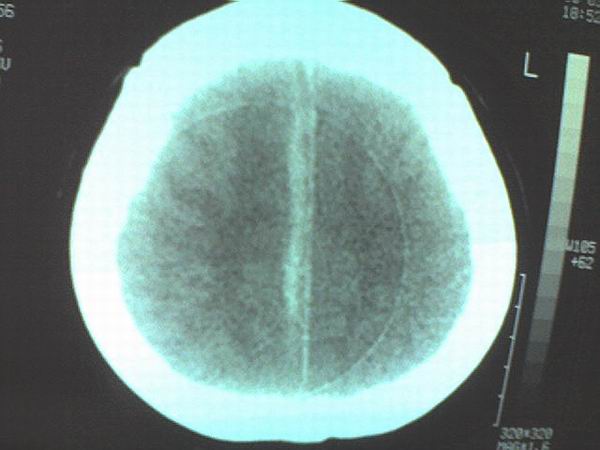

女 43岁 头痛恶心呕吐两天

手机照的,不是太清楚。

右侧大脑镰硬膜下出血

1、右侧大脑镰硬膜下出血2、机器伪影太重,该修修。